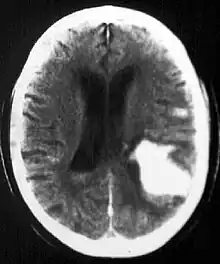

Diagnosis

Computed tomography (CT scan): A CT scan may be normal if it is done soon after the onset of symptoms. A CT scan is the best test to look for bleeding in or around your brain. In some hospitals, a perfusion CT scan may be done to see where the blood is flowing and not flowing in your brain.

Magnetic resonance imaging (MRI scan): A special MRI technique (diffusion MRI) may show evidence of an ischemic stroke within minutes of symptom onset. In some hospitals, a perfusion MRI scan may be done to see where the blood is flowing and not flowing in your brain.